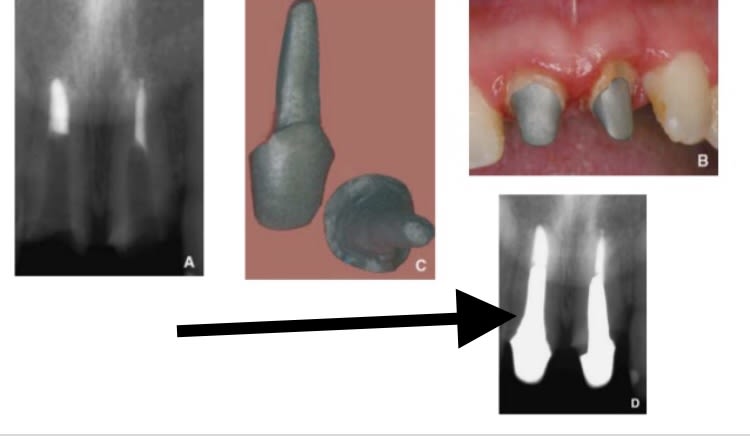

Tiens Molinarus au fait explique moi voir comment tu fais quand tu veux faire un tenon anatomique avec une caméra ? :)))

Comment tu fais pour enregistrer bien comme il faut jusqu’au fond la préparation pour un cône de raccordement ? (Zone où il y a la flèche) car je ne pense pas que tu puisses enregister les imperfections ou les préparations faites en en profondeur avec ta caméra...... comment faites vous pour faire un tenon anatomique en utilisant des caméras ? .